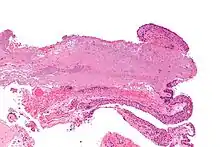

Micrograph of a conjunctiva associated with prominent blood vessels (left-bottom of image) and elastotic collagen (centre of image), as may be seen in a pterygium. H&E stain.

Pterygium in the conjunctiva is characterized by elastotic degeneration of collagen (actinic elastosis[12]) and fibrovascular proliferation. It has an advancing portion called the head of the pterygium, which is connected to the main body of the pterygium by the neck. Sometimes a line of iron deposition can be seen adjacent to the head of the pterygium called Stocker's line. The location of the line can give an indication of the pattern of growth.